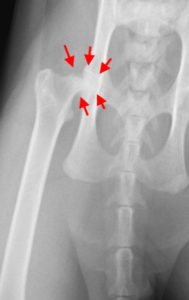

今回も、診察してみると、股関節の痛みがありレントゲンを撮るとやはり、股関節の太腿骨頭の

異常がありました。その後、CTをとり、『太腿骨頭すべり症』と診断し、手術を行いました。

術前:矢印が異常な部分です